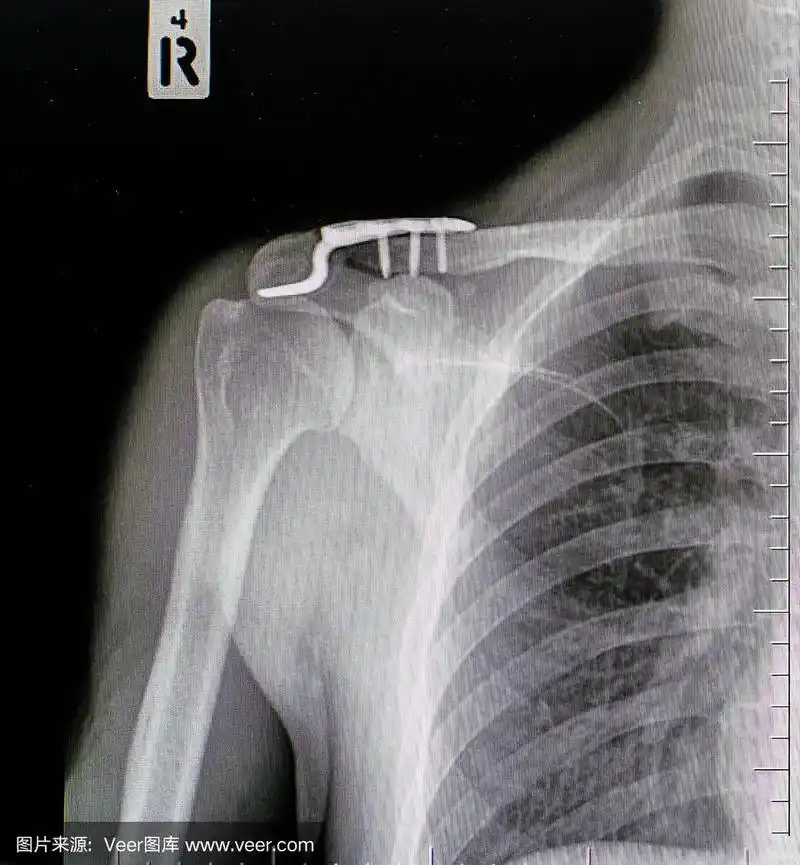

运用mippo技术小切口微创治疗锁骨中段骨折

锁骨骨折x线片,正位片.

右锁骨x线片:右侧骨折

锁骨骨折及肩锁脱位的术后康复